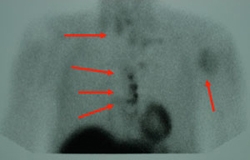

Metastatic parathyroid cancer on sestamibi scan

• Imaging studies – Ultrasound, radioactive tracer (sestamibi) scans, or 4D-CT scans can help localize abnormal glands.